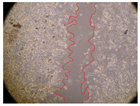

In the present study, the healing potential of 8 decoctions used in the preparation of ayahuasca was evaluated, using the wound scratch test. The evolution of the scratch created was monitored using microscopic images (Table 2) and the distance between the margins of the lesion was calculated (Table 3). Analysing the images that showed the evolution of the distance between the margins of the lesion and comparing them with the control samples, it was possible to verify that, in general, all the samples showed a great decrease in the lesion, and after 24 h of incubation, the samples of M. hostilis + P. harmala at 500 mg/L and P. viridis + B. caapi at 250 mg/L showed the best results. However, analysing the evolution of the distance calculated, only the sample of the commercial mixture at 250 mg/L after 2 h of incubation did not show a significant decrease. All other samples at different evaluation times, as well as the commercial mixture at 250 mg/L at the other times (8 h, 12 h and 24 h) showed a significant decrease in lesion margins compared to the control.

Table 2.

Microscopic images obtained from the scratch wound-healing assay with the samples of ayahuasca (magnification: 100×). The margins of the scratch appear in red.

These results are indicative of the healing activity of the samples tested. It is possible to observe in the images of Table 2 the migration of the fibroblasts incubated with the samples at different concentrations. In these images, it was possible to verify that the lesions closed over time, which was in accordance with the distance calculated between the margins of the lesion. As far as we know, to date there are no studies where the healing potential of ayahuasca has been evaluated, and it is not possible to compare the results now obtained. However, these results can be explained by the antioxidant and anti-inflammatory activity previously studied in these samples [], since it is reported that antioxidant activity and healing properties coexist in plant extracts []. Wound healing consists of the reconstruction of the lesion, involving several interactions between epithelial cells, growth factors, cytokines and chemokines. It has been reported that natural products, namely plant extracts, are involved in the proliferation of fibroblasts and keratinocytes, and may contain cell adhesion molecules, growth factors and cell signalling molecules, which can promote lesion reconstruction []. This in vitro assay, which, unlike conventional assays used to determine the healing properties of plant material, was non-invasive, allowed the screening of several samples with antibacterial, anti-inflammatory and antioxidant properties, which are important in wound healing [,].